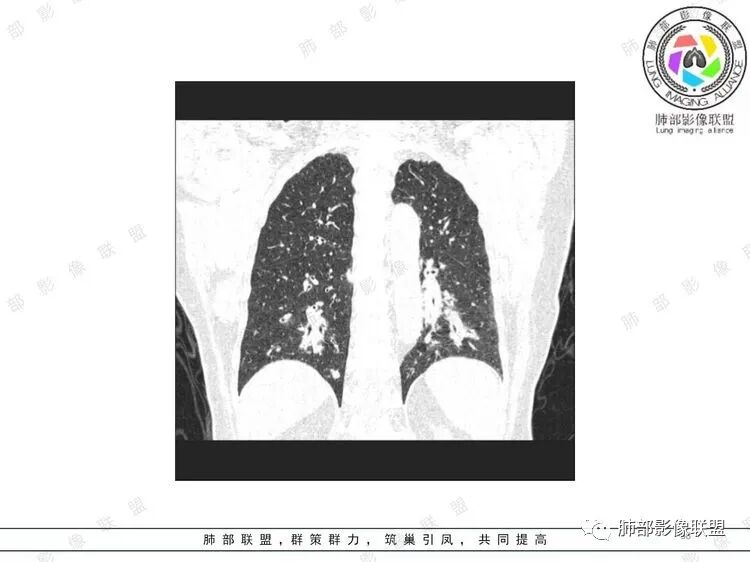

胸CT:双中下肺支气管壁明显增厚,双下肺胸膜下可见实变区。部分病变呈楔形影。

老年女性,咳嗽咳痰低热20天,双肺野散在结节影,随机分布,双肺下叶支气管血管束增粗,支气管管腔狭窄,胸膜下结节斑片影,临床有血尿,痰培养白念阳性,低氧血症。血管炎抗体阴性。从影像看主要侵犯的是血管,血管壁增厚,血管炎抗体阴性不大支持,患者有血尿,考虑膀胱肿瘤引起转移,但是膀胱彩超没发现占位,估计血尿是膀胱炎引起。从影像看考虑侵袭性曲霉菌病?血管炎?实在没有思路。

双肺支气管管壁弥漫性增厚,管腔狭窄,下叶为主,伴多发高密度结节影,边缘模糊,双肺支气管血管束明显增粗,临床症状咳嗽低热,有血尿,首先考虑血管炎

影像上:多发结节沿血管分布;双下叶支气管血管束简直增厚,偏血管,支气管通畅